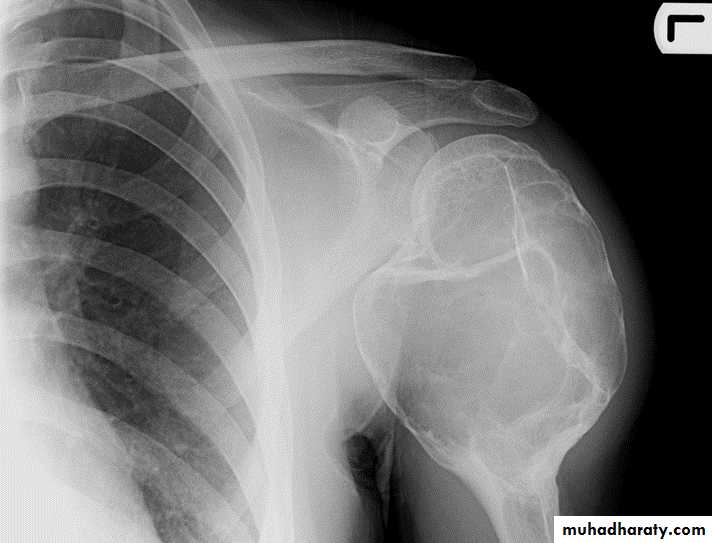

Chondrosarcoma :

Age: 30-50yrs.Site: pelvic bones, scapula, humerus, femur.

May arise as malignant degeneration in cartilage cap of osteochondroma (1%) and in its benign counterpart enchondroma .

Findings:

Ill-defined expanding lytic lesion

Flecks of calcification.

May have periosteal reaction.

Large extra osseous component.